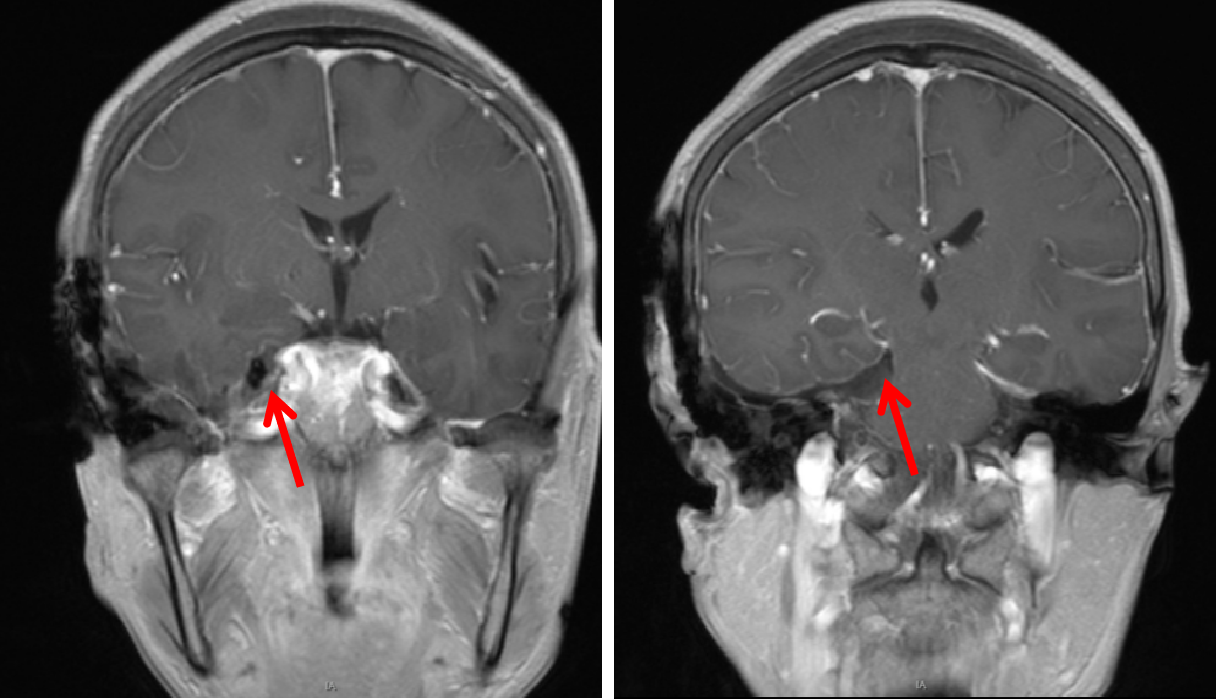

术前磁共振检查诊断:右侧岩尖脑膜瘤、继发性右侧TN;

术前MRI提示肿瘤位于右侧岩尖,压迫脑干及三叉神经。

术前磁共振轴位增强

术前磁共振冠状位增强

术后增强示肿瘤全切